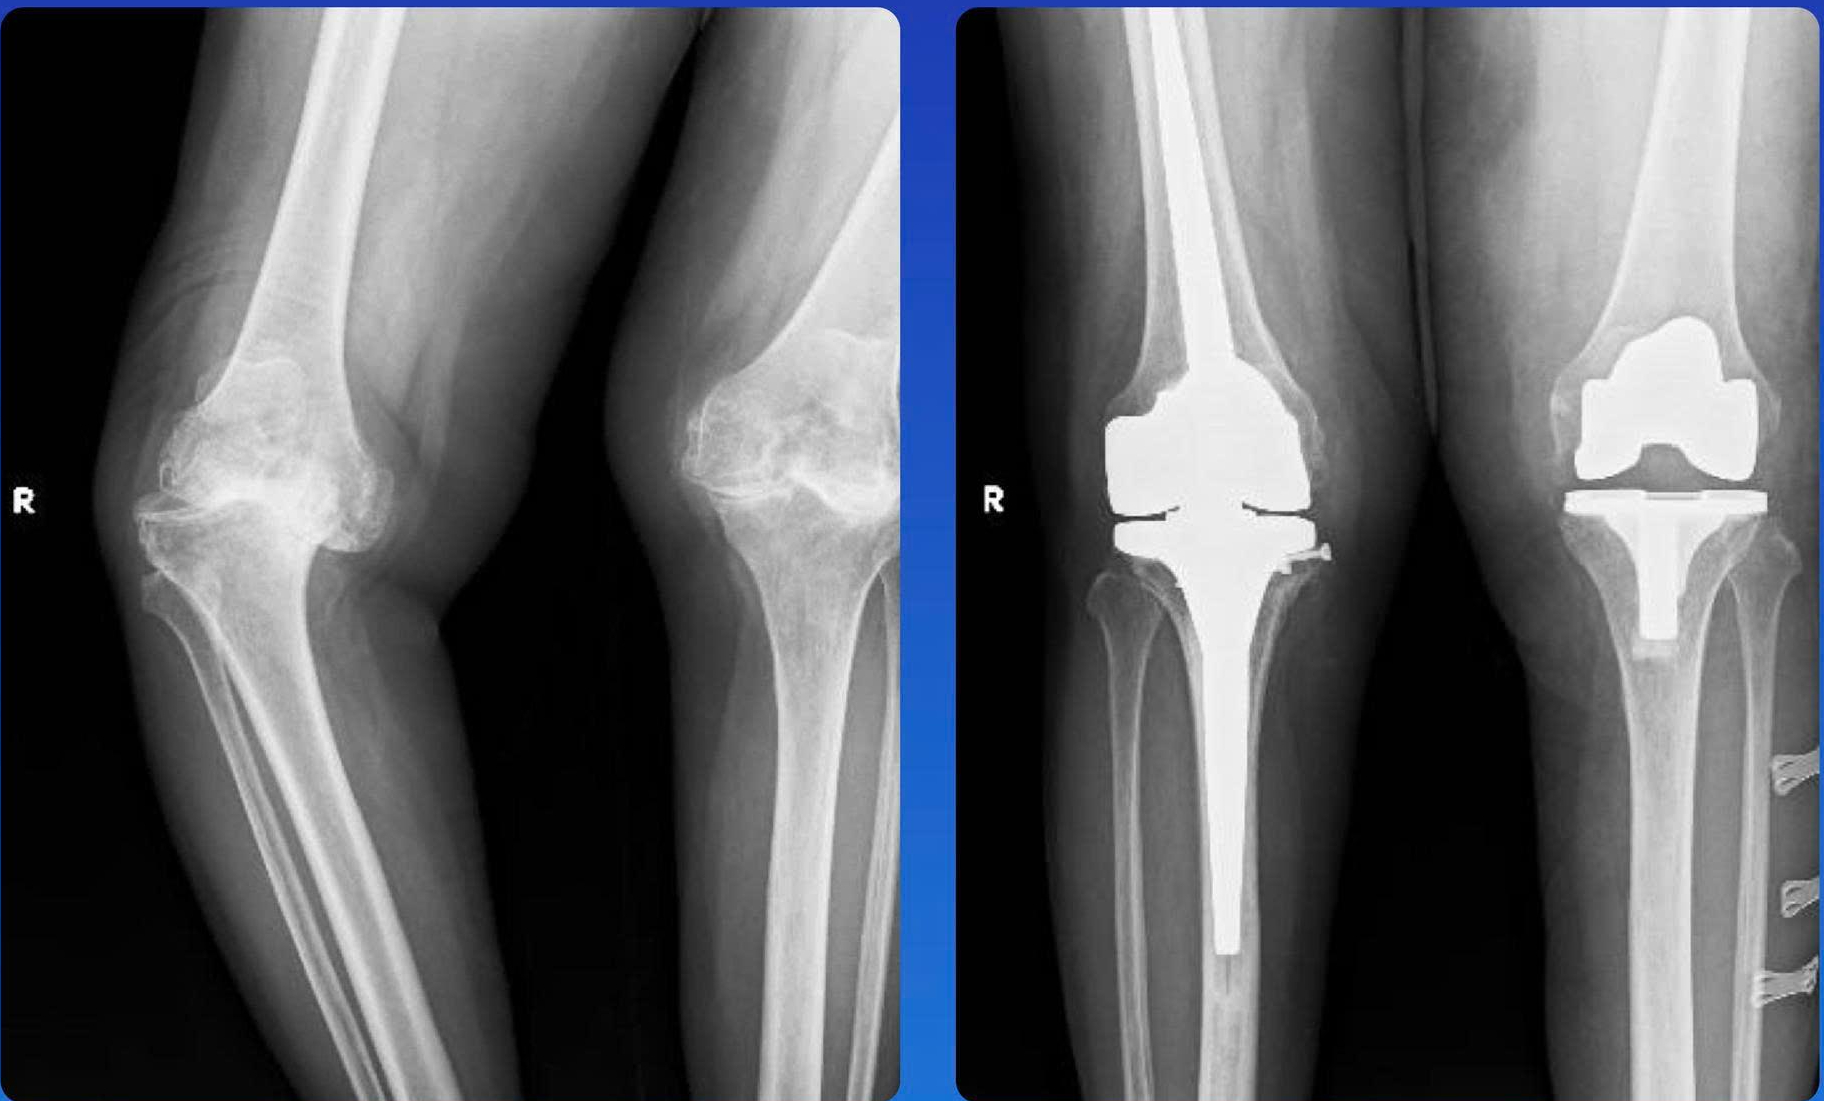

Sendi lutut pasien wanita berusia 69 tahun sebelum (kiri) dan setelah operasi penggantian sendi engsel - Foto: THUONG HIEN

Sebelumnya Ibu X pernah dirawat di rumah sakit dengan keluhan kelainan sendi berat, lutut kanan bengkok ke dalam 40 derajat, lutut kiri bengkok ke luar, disertai nyeri hebat dan tidak stabil saat digerakkan.

Pada bulan Juni, ia menjalani operasi penggantian lutut kanan, diikuti dengan operasi penggantian lutut total pada lutut kirinya pada bulan Agustus. Setelah menjalani rehabilitasi selama lima hari, ia dapat berjalan normal dan diperbolehkan pulang dari rumah sakit.

Menurut Dr. Nguyen Nguyen Thai Bao, kepala Departemen Bedah Sendi - Kedokteran Olahraga di Rumah Sakit Pusat Hue, sendi lutut engsel merupakan jenis sendi khusus, yang cocok untuk kasus rumit akibat kelainan bentuk yang parah atau hilangnya fungsi ligamen, yang memerlukan teknik tinggi untuk memastikan stabilitas dan memulihkan mobilitas.